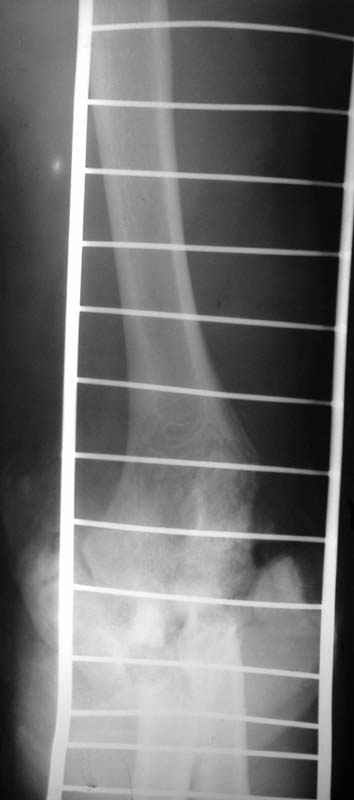

Операция - ПХО, ЧКО АВФ (см.приложение).

Репонировать фрагменты локтевой и плечевой кости не представилось возможным (по сути <каша> из мелких осколков сомнительной жизнеспособности), резекция головки лучевой кости, иссекли мягкие ткани, кожа зашита почти без натяжения, дренажи, АВФ.

Иногда на Rg-граммах - "суповой набор", а объем движений очень приличный...

Лечение, видимо - оперативное пособие по необходимости и раняя разработка сустава.